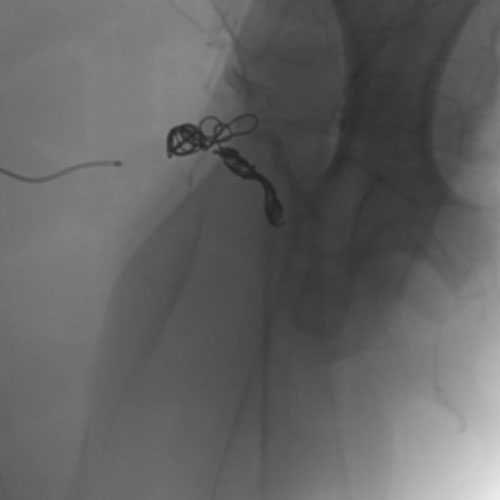

Embold Fibered Coil shown in left internal iliac artery Embold Fibered Coil shown in left internal iliac artery

Left Internal Iliac Artery

3 Embold Fibered Coil 6x20